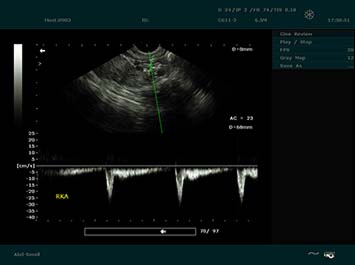

Imágenes Clínicas